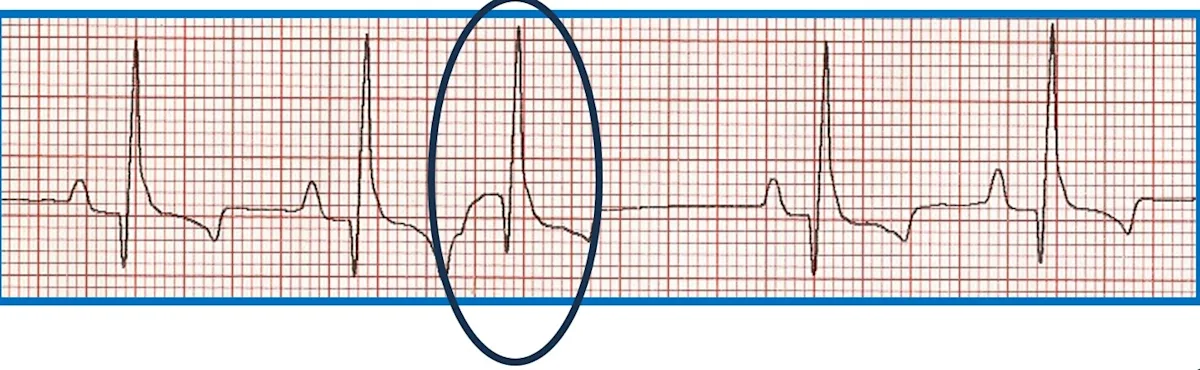

FIGURE 6 Effect of ectopic foci origination location on ECG appearance. (A) ECG showing a normal QRS complex but indiscernible P wave (circle) characteristic of premature beats with supraventricular origin; the circled premature beat is almost identical to the beats with an associated P wave. (B) Illustration demonstrating where ectopic foci result in supraventricular (above dotted line) and ventricular (below dotted line) ECG patterns. (C) ECG showing no P wave; a wide, bizarre QRS complex; and a large, bizarre T wave (circles) characteristic of premature beats with a ventricular origin.